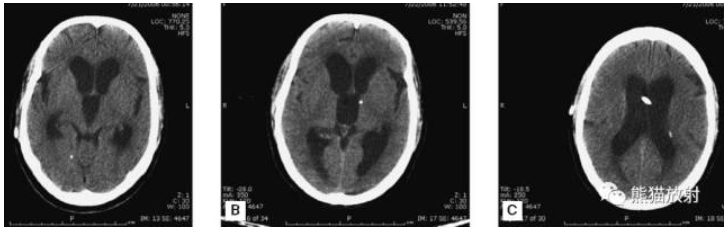

颅脑CT常用的三个窗(图A-C):

图A:骨窗(the bone window)

图B:脑窗(the brain window)

图C:血窗(the blood window)

图A:骨窗;主要用于明确骨折、窦腔病变、颅内积气。

图B:脑窗;可清晰显示灰白质,可发现中风的早期征象或其他导致脑水肿等表现的病变。

图C:血窗;更利于显示硬膜下或颅内出血。

本例表现:骨窗示:右顶骨骨折;三个窗均示:软组织水肿并皮下积气;血窗:少量硬膜下血肿。